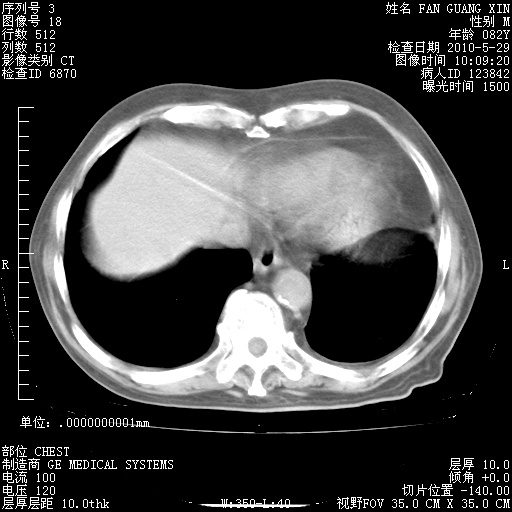

再治疗10天后的肺部CT

阅读此次胸部CT,肺间质渗出性改变较入院时有吸收。目前从体温、白细胞、中性分叶明显增高,肯定存在细菌感染(发生医院感染哦,若无消化道及泌尿系统等感染的依据,肺部感染可能大)。若你院头孢哌酮舒巴坦钠耐药率较高,同意你的方案,若48小时体温仍高,可考虑使用碳青霉稀类抗菌药物,同时可予超声雾化、注意滴数时加大液体量。白蛋白33.30g/L较低哦,需加强营养等支持治疗。